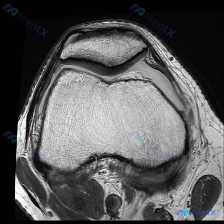

今天看到一个很有代表性的读片问题,整理出来和大家分享讨论:问题是判断这张髌股关节轴位T1加权MRI上有没有软骨异常,我们一步步梳理思路。 一、先看影像基本信息 这是一张膝关节MRI的轴位T1加权图像,扫描层面位于膝关节上方的髌股关节层面: 1. 骨骼结构:髌骨位于前方,骨皮质边缘清晰,骨髓脂肪信号正...

看到这个挺有代表性的读片病例,整理一下资料和分析思路分享给大家。 病例基础信息 这是一份单张膝关节MRI轴位T1加权序列影像,临床怀疑存在软骨异常,要求读片分析。 影像学读片结果 解剖结构评估 1. 骨性结构:髌骨形态完整,皮质连续,骨髓信号无异常;髌股关节对合关系大致正常,无半脱位;股骨远端滑车区...

今天遇到一个有意思的读片问题:只给了一张膝关节轴位MRI,问这里有没有软骨异常,整理一下分析思路分享给大家。 基本病例/影像信息 提供的是膝关节单张轴位MRI扫描图像,可识别的解剖结构包括:前方的髌骨、中部的股骨内外侧髁与髁间窝、髌股关节间隙,以及周围部分软组织。 客观影像所见 1. 软骨结构:髌骨...

看到一个很有讨论意义的膝关节影像病例,整理出来和大家分享一下。 病例基本信息 核心问题:临床怀疑存在膝关节软骨异常,仅提供单张膝关节MRI T1序列轴位影像进行分析。 影像学读片结果 这张影像为髌股关节层面的轴位T1加权像,读片结果如下: 1. 骨骼结构:髌骨、股骨内外侧髁形态完整,皮质骨连续,松质...

最近遇到一个有意思的读片病例:临床怀疑髌股关节软骨异常,但给出的单张T1加权轴位MRI却没看到明确病灶,整理一下整个分析思路分享给大家。 一、病例影像基础信息 这是一份膝关节MRI检查的T1加权轴位(横断面)图像,扫描层面位于髌股关节水平,先整理一下基础读片结果: 1. 解剖结构确认:前方为髌骨,后...